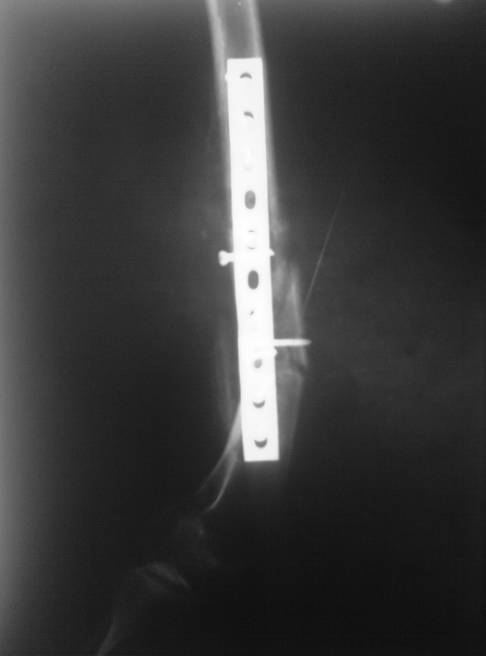

Травма в декабре 2006 года. Диагноз: Сочетанная травма. ЗЧМТ. Ушиб мозга. Кома. Закр. перелом левой плечевой кости; левой лучевой кости; оск. перелом левой бедренной кости.

Оперирована в январе 2007 года по выходе из комы и восстановления витальных функций. Накостный остеосинтез DCP-LC. Снимки прилагаются.

Через 4 месяца стали беспокоить боли и деформация бедра. На снимке угловая деформация AP - варус 11 град.; lateral - 29 град. Объем движений в коленном суставе: ограничение сгибания до 90 град. Локально - патологическая подвижность в нижней трети бедра. Локальная гипертермия, отек мягких тканей. Гиперемии нет. Передвигалась на костылях.